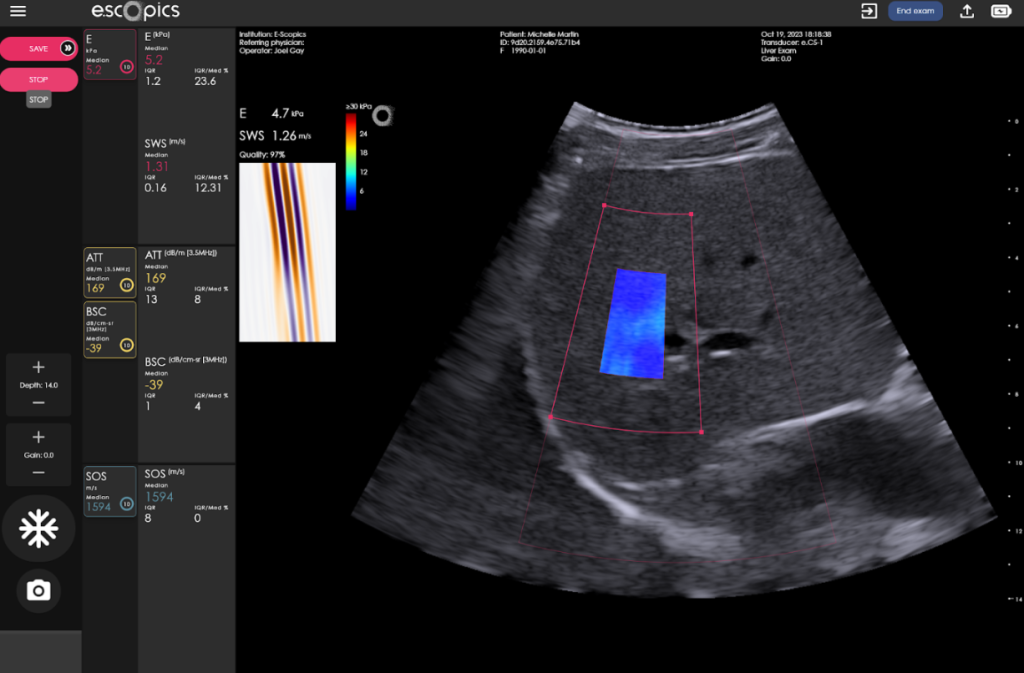

Hepatoscope 2DTE (two-dimensional transient elastography) is a breakthrough ultrasound technology for liver stiffness measurement (LSM), integrating both transient elastography (Catheline, Wu, and Fink 1999) and ultrafast ultrasound (Tanter and Fink 2014), implemented in an ultraportable format. It is the successful result of years of development and integrates more than ten patents. Powered only through a computer’s USB-C port, Hepatoscope has resolved many technical challenges, including power efficiency, data rate reduction, and portability.

This is why Hepatoscope 2DTE has been developed. It stands on the shoulders of both

transient elastography for shear wave generation with ultrafast imaging to track shear wave propagation.

A shear wave is generated with an external vibrating mass centered at 50Hz, as for other forms of transient elastography (VCTE, ViTE…).

Inspired by the SSI technique, Hepatoscope tracks in two dimensions the tissue displacements induced by shear waves along their propagation direction.

This avoids refraction biases and enables the display of liver stiffness imaging and leads to robust stiffness estimation as a large portion of the liver is sampled.